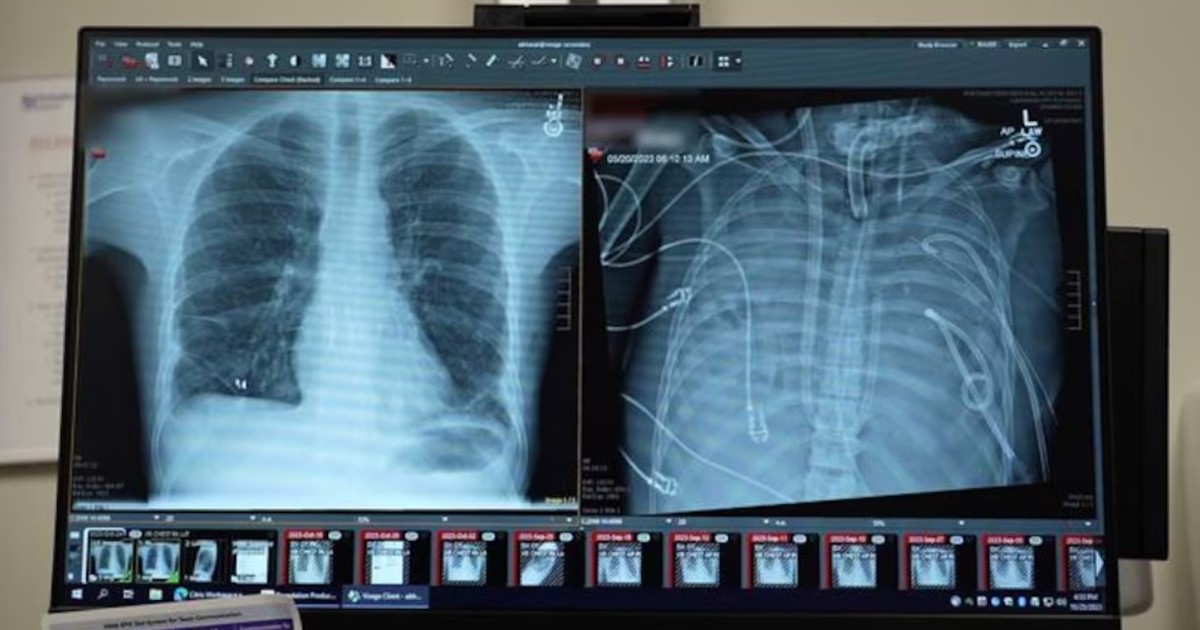

Un equipo médico de Estados Unidos mantuvo con vida a un joven de 33 años con un sistema de pulmón artificial hasta hallar donante para un trasplante doble.